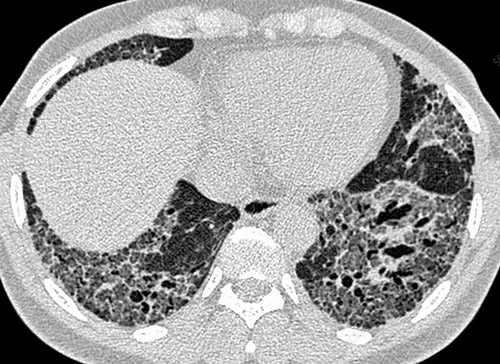

КТ ОГК. Интерстициальная пневмония, участки «матового стекла» (красная стрелка) и ретикулярные изменения.

- Рентгенография. Рентгенологическими признаками интерстициальной пневмонии могут являться симметричные полупрозрачные затемнения по типу «матового стекла», в основном в нижних отделах легких; утолщение междолькового и внутридолькового интерстиция; кистозно-фиброзные изменения, периваскулярная и перибронхиальная инфильтрация и тракционные бронхоэктазы.

- КТ высокого разрешения. Помогает уточнить распространенность поражения легочной ткани, оценить стадию, активность и темпы прогрессирования фиброзного процесса.